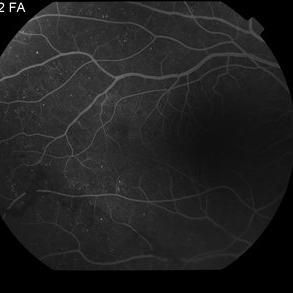

Proliferative Diabetic Retinopathy with Vitreous Hemorrhage - FA

Oct 18 2012 by Suber S. Huang, MD, MBA, FASRS

30 year old diabetic man with proliferative diabetic retinopathy and vitreous hemorrhage

Photographer: Stacie Hrvatin

Condition/keywords: cotton wool spots, neovascularization (NV), subhyaloid hemorrhage, vitreous hemorrhage